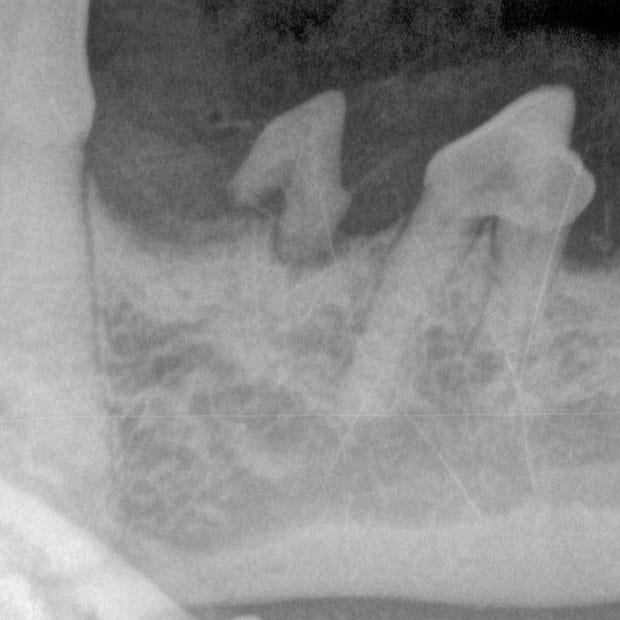

Dental Radiographs (X-rays):

- X-rays are crucial for diagnosing issues not visible to the naked eye, such as tooth root abscesses, bone loss, or retained roots. They guide our treatment plan for optimal outcomes.